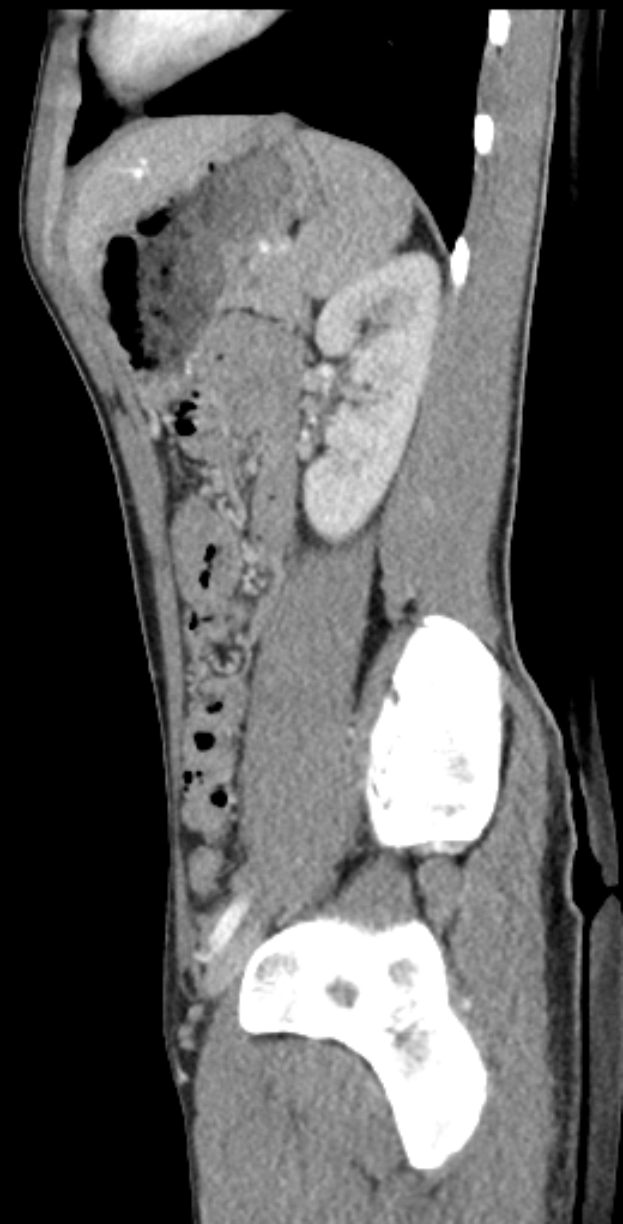

Eine MRT-Aufnahme eines Knies mit einem Bruch in der Mitte, umgeben von einem dunklen Hintergrund.Jonas Günther